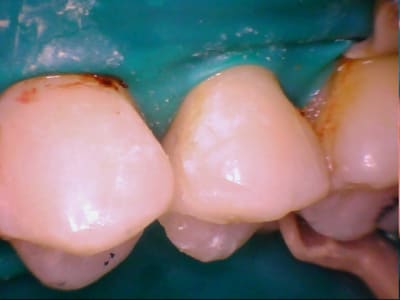

Bonjr! récente recrue sur le forum,jsuis ortho exclu et mon chir dent a proposé à mon homme un IC et une ccm pour sa 45... ça me semble un peu invasif...

-endo RAS bien que vieille

-pan lingual intact et le vestib. quasi

(quand c'est les siens bizarrement on bugue...)

Bon d'ac. dent dévitalisée=fragile=risque de fracture blabla

Perso elle pas belle (noircie) mais c'est la sienne et il est assez couronné comme ça

qu'est ce que vs en pensez? des Idées?

Il aurait fallu une photo en vue occlusale. D'après ce que je vois, un joli composite direct doit être largement suffisant. Les prémolaires du bas sont des dents qui se cassent rarement, surtout s'il n'y a qu'une cavité proximale et non MOD (en plus, largement supragingivale)

Il n'y a pas qq chose de louche au mésial de la 47 ?

et comme ceramik, il y a un truc louche sur 47

Refaire aussi la 47 (reprise de carie) et la 46 qui sont dégueulasses.

Pour la 45, un truc sans tenon (soir un compo direct avant de prendre l'empreinte pour 46, soit un inlay).

Comme Marc, les prémol du bas se fracturent rarement, mais ça arrive quand même...